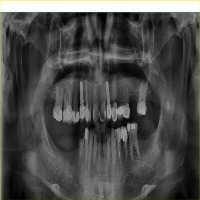

vzrad2 Computer Vision Project

Arshs Workspace Radio

downloadsClasses (93)

Amalgam filling

Bone Loss

Calculus

Caries

Cavity

Composite filling

Crown

Cyst

Implant

Periapical lesion

Root canal filling

A description for this project has not been published yet.